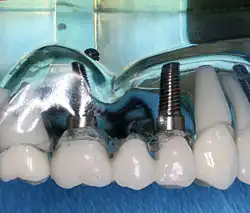

Bei einem minimalinvasiven Vorgehen wird das Implantatbett für das Miniimplantat präpariert, ohne einen Mukoperiostlappen zu bilden. Die vereinfachte und kürzere Operation kann eventuelle postoperative Beschwerden reduzieren. Orientierungshilfe bietet eine Bohrschablone.[42]

-

Implantat-Bohrschablone intraoral bei Implantation (Aufsicht)

Implantat-Bohrschablone intraoral bei Implantation (Aufsicht) -

Implantat-Bohrschablone intraoral bei Implantation (Ansicht von vorne)

Implantat-Bohrschablone intraoral bei Implantation (Ansicht von vorne) -

Implantat-Bohrschablone intraoral bei Implantation (Aufsicht)

Implantat-Bohrschablone intraoral bei Implantation (Aufsicht)